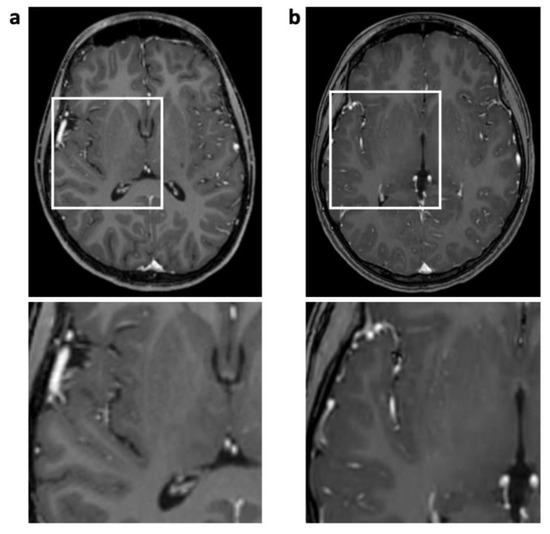

Figure 2.

Enhanced 3D T1 TFE images of an 18-year-old male patient with ganglioglioma (not shown). Reconstruction artifact with thin oblique geometrical streaks is seen in SENSE 3D T1 TFE ((a), post-surgery); not present in CS 3D T1 TFE (b). White box indicates magnification.